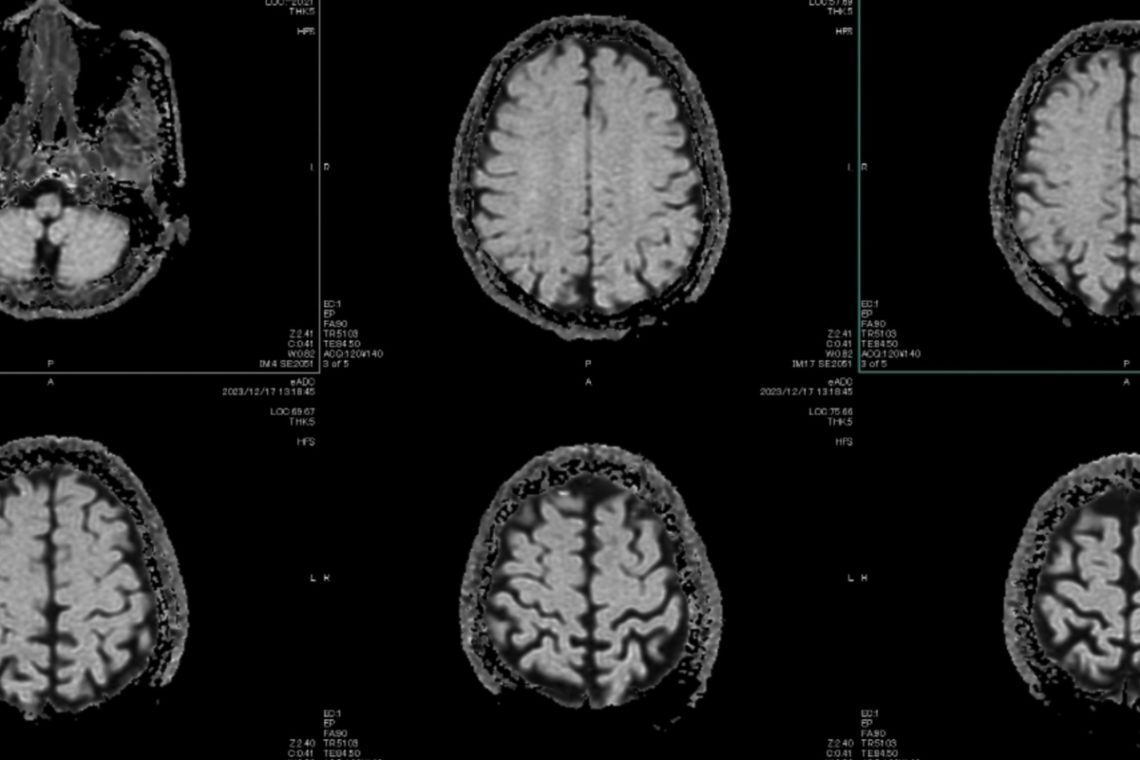

Researchers compared data and MRI scans in order to analyze participants’ brain volume. That allowed the scientists to compare gray matter levels and label structures in the brain.

Overworked individuals exhibited a 19 percent increase in volume in the left caudal middle frontal gyrus portion of the brain, as well as peak volume increases in 17 regions of the brain, when compared to non-overworked people.